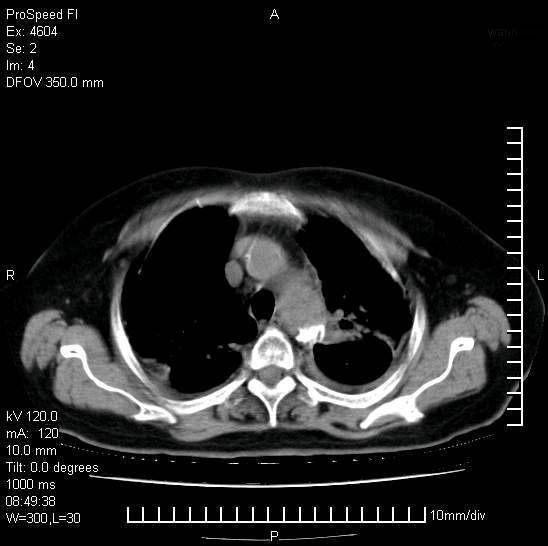

标题: CT15528:女性,79岁,近几日晚上高热,39度,仍咳少量血

十几年前曾患肺结核,一周前突咳血约100ml,中性粒细胞稍高,诊断两上肺陈旧结核,下肺炎症,给予抗炎治疗,近几日晚上高热,39度,仍咳少量血,4天前ct及今天ct上传。

今天ct

1)两肺结核并感染。2)不排除左肺上叶中央型肺癌并阻塞性肺炎、肺不张可能;建议行纤支镜检查。3)右肺门及纵隔淋巴结肿大。4)双侧胸腔积液。